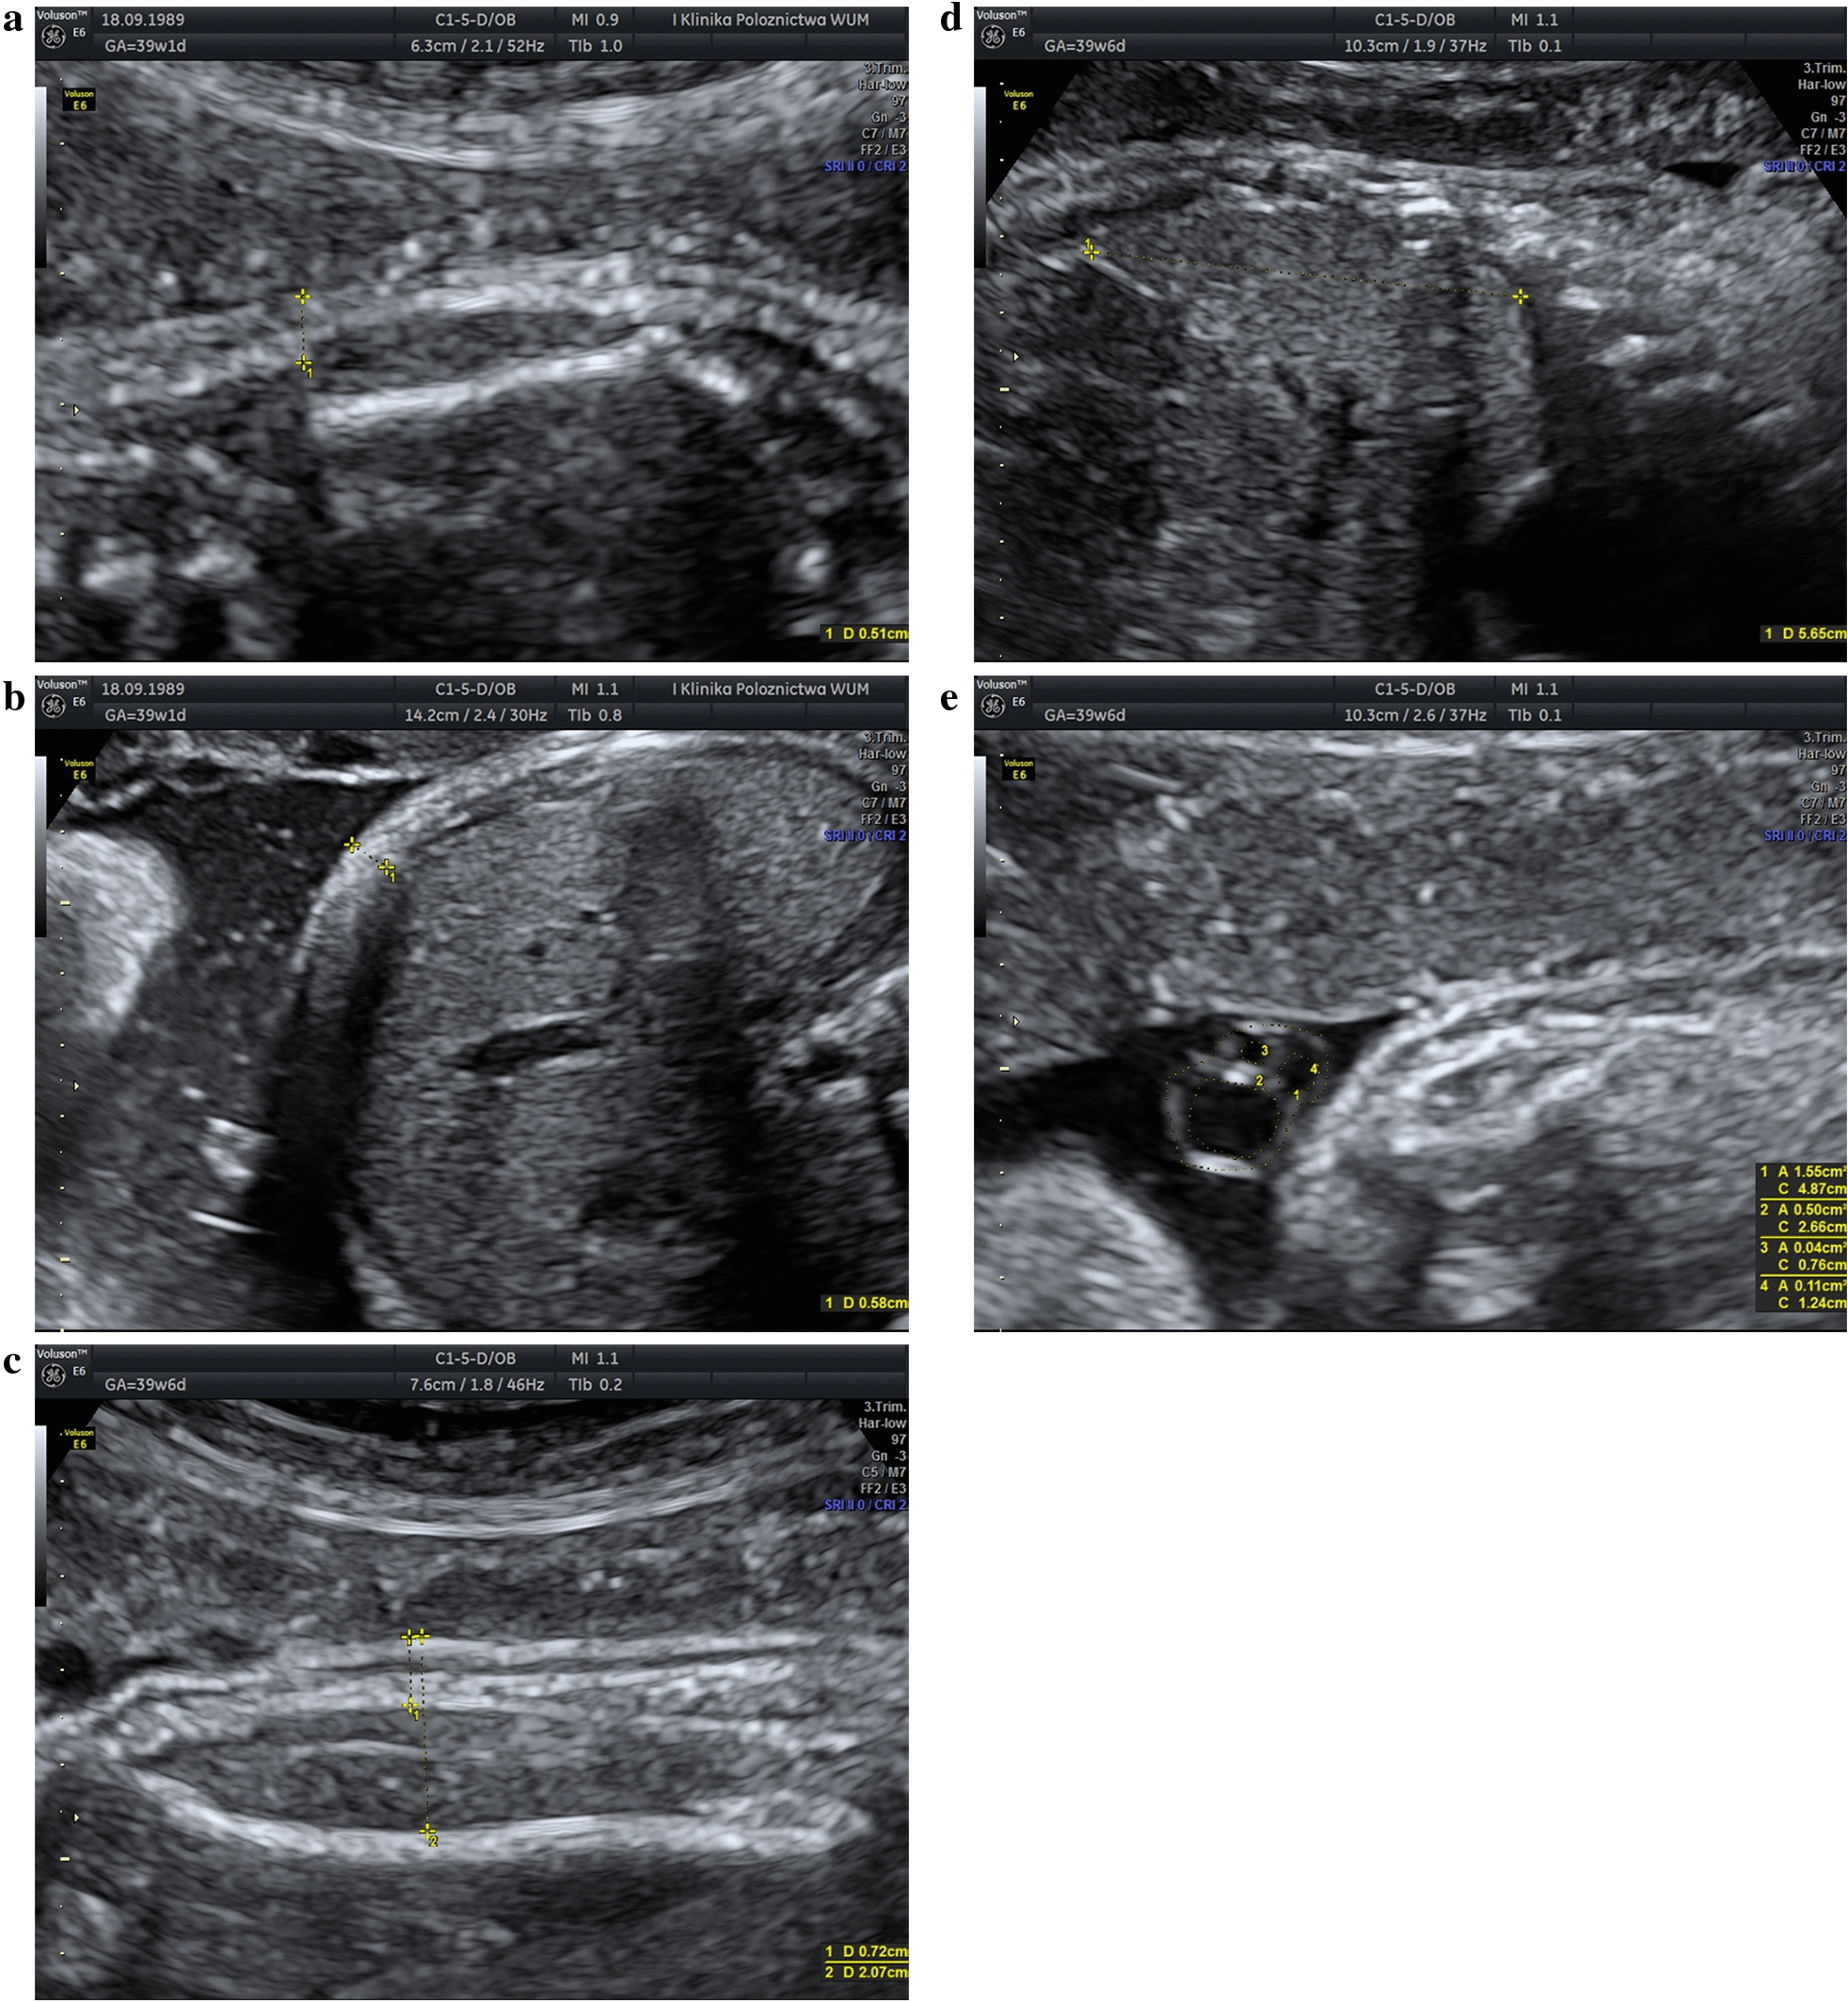

For the SSFM measurement, the sagittal section of the fetal trunk was obtained, visualizing the entire scapula, with one caliper placed on the skin surface and the second caliper placed at the level of the subcutaneous tissue, perpendicularly to the bone at its distal end (Fig. 1a) [ref. 19, ref. 33]. The AFM was determined by measuring the thickness of the anterior abdominal subcutaneous tissue. A transverse section of the fetal trunk at the level of the umbilical cord was obtained, with the fetal abdomen free from contact with extremities and with the amniotic fluid between the fetus and the uterine wall. The first caliper was placed between the amniotic fluid and the fetal skin, and the second one between the subcutaneous fat tissue and the fetal liver (Fig. 1b) [ref. 19, ref. 33]. The MTFM and MTLM parameters were evaluated in the standard longitudinal section used for femur length measurement, in the middle of the fetal thigh [ref. 16]. For both MTFM and MTLM measurements the first caliper was placed on the skin surface, and the second caliper was placed at the level of the subcutaneous tissue (MTFM), or at the outer margin of the femur (MTLM) (Fig. 1c). The HeC/HeA and ThC/ThA measurements were performed after a good four-chamber view with complete ribs on both sides of the thorax was obtained, during heart diastole, and using the ellipse method, as described by Awadh et al. [ref. 34]. The IVS thickness was measured halfway between the apex and the crux of the heart, during maximum ventricular filling, with the septum positioned horizontally [ref. 18]. To determine the LL, the sagittal plane of the fetal abdomen was visualized and the diameter between the right hemidiaphragm dome and the tip of the right lobe was measured (Fig. 1d) [ref. 17, ref. 21, ref. 22]. For evaluation of the umbilical cord parameters, a cross-sectional view of a free loop was obtained and measurements of the UmC/UmA, UvC/UvA and UaC/UaA were performed using the software of the ultrasound device, as previously described (Fig. 1e) [ref. 28, ref. 35]. The sum of three vessel areas constituted the UveA, and WjA was calculated by subtracting the UveA from the UmA. For statistical comparisons, the mean values of the UaC/UaA were calculated for each patient (mUaC/mUaA).